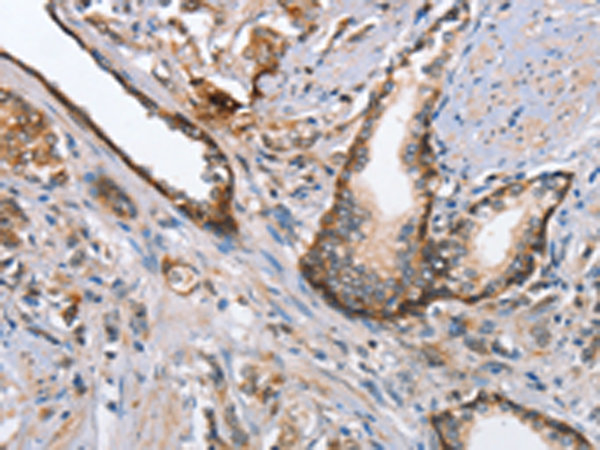

分类: 科研抗体货号: P07409别名: ARM1; EMSP; PSTS; AI2A1; EMSP1; KLK-L1; PRSS17; kallikrein应用: IHC反应种属: Human